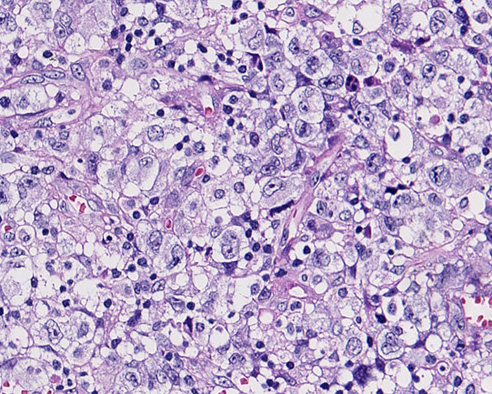

病理形態学的所見†

- 馬蹄形(偏心性), 腎臓様, またはドーナツ状などの核をもつ目印細胞「hallmark cells」をさがす。

- hallmark cellsは通常大型であるが、小型のものも存在する。

- しばしば核近傍に好酸性のゴルジ野が見つかる。(CD30, ALK染色などで陽性となる)

- 形態学的亜形が存在することに注意。小型腫瘍細胞からなるものから巨核あるいは花環状の多核細胞からなるものまである。

- 形態にかかわらず核クロマチンは繊細で、あまりめだたない。(明るい核が多い). 核小体は複数個で不規則。

- リンパ節内では実質内にびまん性分布をしめす。しばしば類洞浸潤が特徴的。

- 腫瘍細胞は結合性,粘着性で, organized patternをとって増殖し, 未分化癌や悪性黒色腫の転移と誤診断することがある。

- 背景に好中球浸潤, 形質細胞浸潤を伴うことあり。 好酸球浸潤や類上皮細胞反応はまれ。